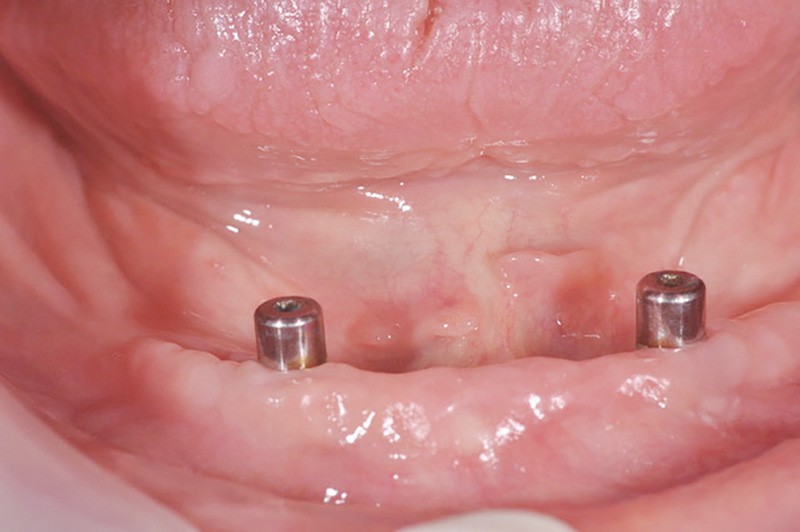

Au bout de trois mois, les vis de cicatrisation sont déposées (fig. 8), des piliers implantaires (patrices) Locator R-Tx sont choisis et vissés à 20 Ncm (fig. 9 et 10a-c).